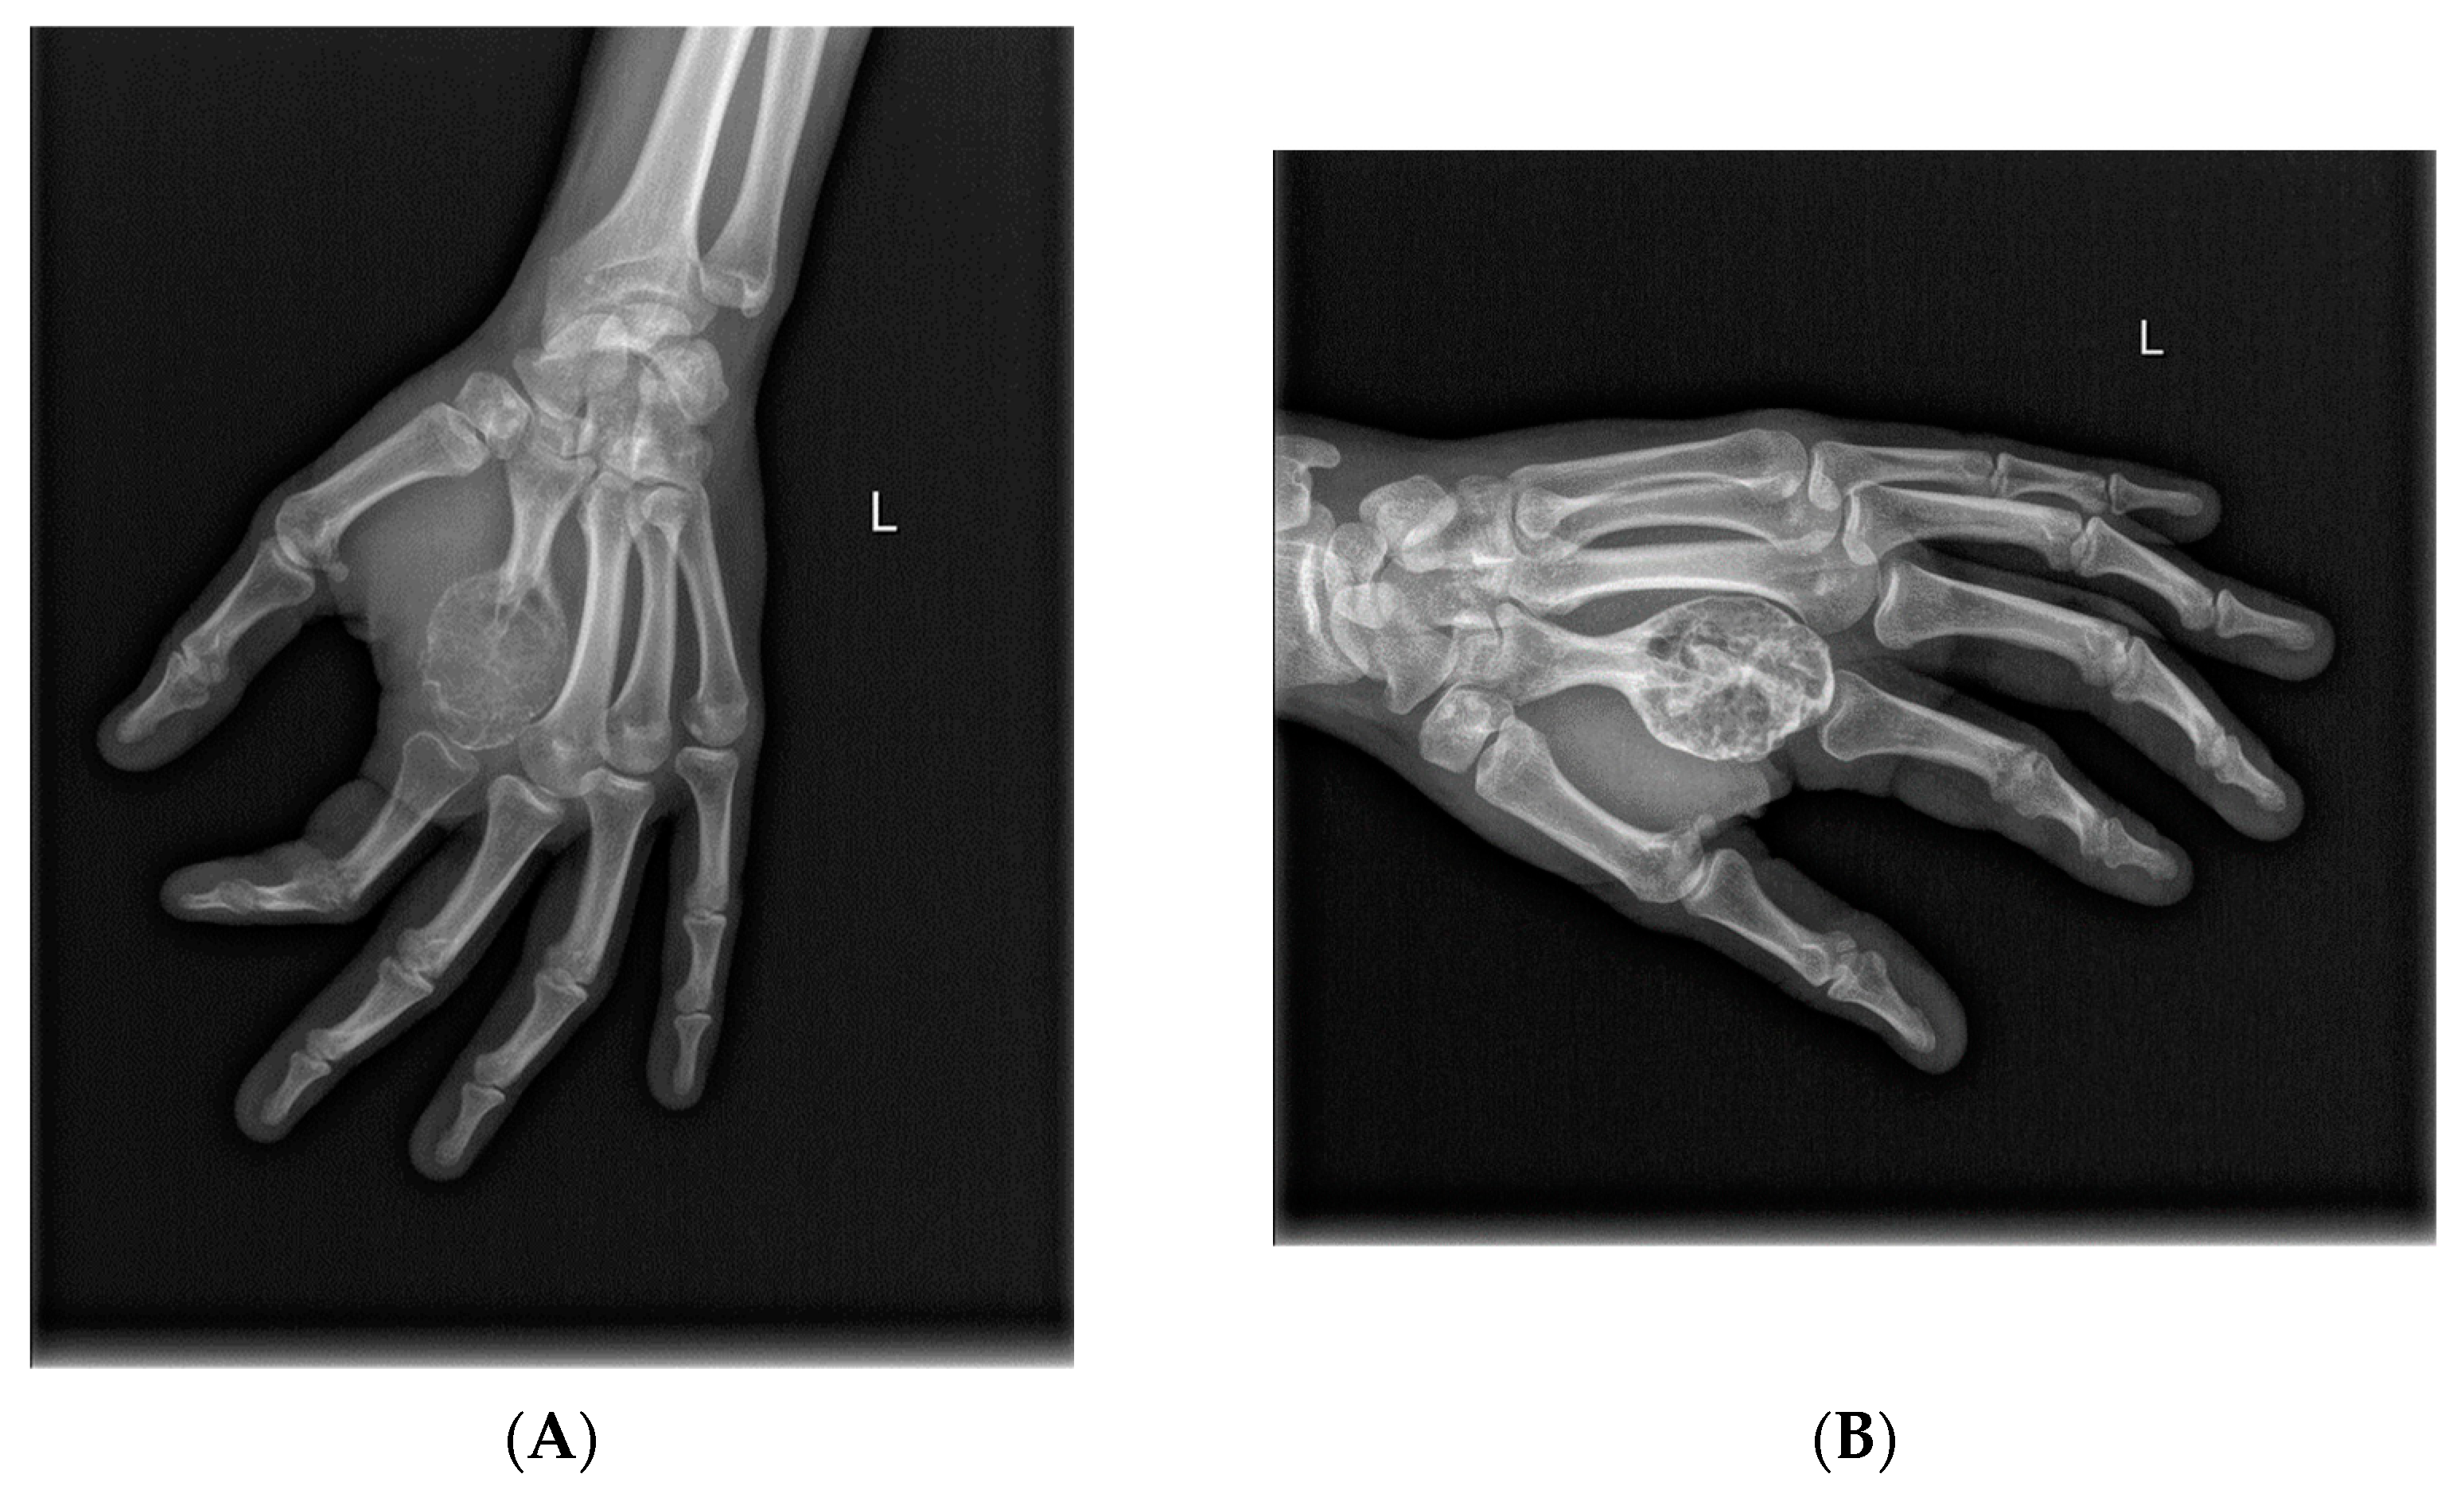

- Van Langevelde, K.; McCarthy, C.L. Radiological findings of denosumab treatment for giant cell tumours of bone. Skelet. Radiol. 2020, 49, 1345–1358. [Google Scholar] [CrossRef] [PubMed]

- Murphey, M.D.; Nomikos, G.C.; Flemming, D.J.; Gannon, F.H.; Temple, H.T.; Kransdorf, M.J. Imaging of Giant Cell Tumor and Giant Cell Reparative Granuloma of Bone: Radiologic-Pathologic Correlation. RadioGraphics 2001, 21, 1283–1309. [Google Scholar] [CrossRef]

- Oguro, S.; Okuda, S.; Sugiura, H.; Matsumoto, S.; Sasaki, A.; Susa, M.; Morioka, H.; Jinzaki, M. Giant Cell Tumors of the Bone: Changes in Image Features after Denosumab Administration. Magn. Reson. Med. Sci. 2018, 17, 325–330. [Google Scholar] [CrossRef]

- Hakozaki, M.; Tajino, T.; Yamada, H.; Hasegawa, O.; Tasaki, K.; Watanabe, K.; Konno, S. Radiological and pathological characteristics of giant cell tumor of bone treated with denosumab. Diagn. Pathol. 2014, 9, 111. [Google Scholar] [CrossRef]